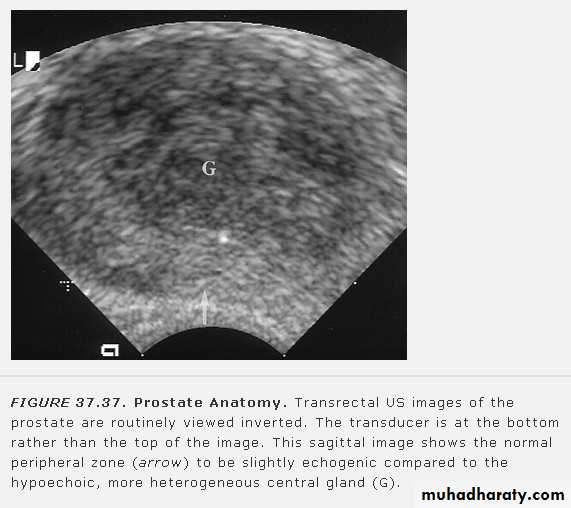

• Prostatic enlargement is very common in elderly men. It is usually due to benign prostatic hypertrophy but may be due to carcinoma.• TRUS: can show the overall size of the prostate and can diagnose relatively small masses within its substance. TRUS-guided biopsy is used for the diagnosis of prostatic carcinoma

• Trans-abdominal US: used for assessment the size and volume of prostate(the normal prostatic volume is < 20 ml) , measurment of post voiding residual urine volume and determine if there is associated development of hydronephrosis.

• MRI: the zonal anatomy of prostate is very well demonstated by MRI. In T2 images, the peripheral zone(the most common origin of tumors) is of high signal intensity and the tumor is of low signal intensity. MRI is used to assess early stage prostatic cancer in patients being considered for radical surgery or radiotherapy. MRI is also used to demonstrate extracapsular tumor spread, to show invasion of the seminal vesicles, and to demonstrate possible LN metastases.

• CT: does not demonstrate the internal structure of the prostate as well as TRUS or MRI.